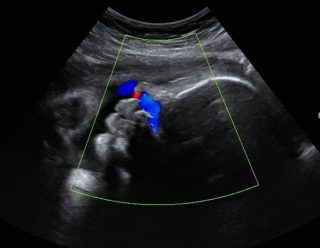

سونوگرافی بیوفیزیكال پروفایل( BPP or BPS) Biophysical Profile

بیوفیزیکال پروفایل یک آزمایش ساده مبتنی بر سونوگرافی است که در دوران بارداری برای ارزیابی سلامت کودک شما استفاده میشود. این آزمایش به طور عمده در سه ماهه سوم برای ارزیابی اینکه کودک شما اکسیژن و تغذیه کافی از جفت دریافت میکند یا نه انجام میشود.

سپس برای انجام سونوگرافی بیوفیزیكال پروفایل مادر به اتاق سونوگرافی منتقل شده تا چهار مولفه دیگر در طول معاینه بیوفیزیکال بررسی شود. هر مولفه مطابق با معیارهایی است که در جدول زیر ذکر شده است، در كل برای هر پنج مولفه تا سقف 2 امتیاز داده میشود.. سپس امتیازات برای حداکثر نمره 10 ثبت میشوند.